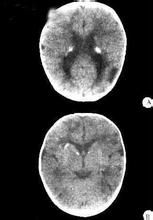

torch綜合症但在妊娠早期,胎盤屏障發育不全,因此,母親一旦感染病毒,就會毫無阻礙地損害到胎兒,重則流產,輕則致畸,不論後果如何,都是我們所不願意看到的,所以專家們要求大家在準備懷孕之前,做一個病毒抗體檢查,是很有道理的。